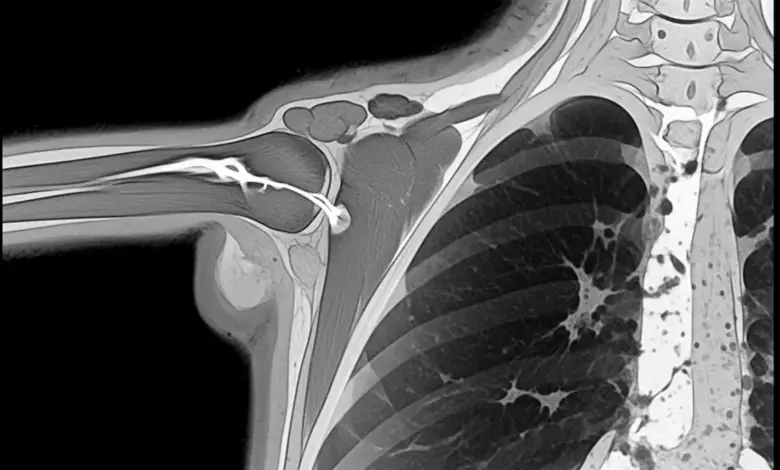

- Ressonância magnética: exame mais completo para ruptura completa do manguito rotador, pois define o tamanho, retração, tendões envolvidos e sinais de degeneração muscular, dados importantes para planejar o tratamento.